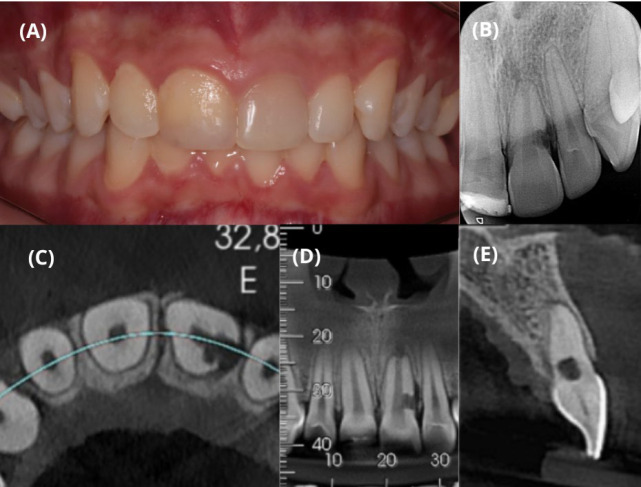

侵袭性牙颈部吸收(ICR)是一种侵袭性病理状态,可影响任何恒牙。这一过程的特点是肉芽肿性纤维血管组织或纤维骨组织取代牙齿结构。尽管无症状,但 ICR 可导致牙齿脱落。本研究报告了一例有牙齿外伤史的 15 岁男孩的 ICR 病例。患者被诊断为 21 号牙齿的 ICR。在考虑了外部手术方法和专门的牙髓治疗的风险后,我们提出了意向性再植结合口外复合树脂修复和牙髓治疗的方案。手术包括无创伤拔牙、清除肉芽肿组织、用复合树脂修复牙洞、在牙槽内重新种植牙齿以及牙髓治疗。经过 3 年多的随访观察,这种方法令人满意地修复了吸收性病变。本病例强调了有意再植结合适当的牙髓治疗是治疗 ICR 的可行方案。

Invasive cervical resorption (ICR) is an aggressive pathological condition that can affect any permanent tooth. This process is characterized by replacement of the tooth structure with granulomatous fibrovascular or fibro-osseous tissue. Despite its asymptomatic nature, ICR can lead to tooth loss. This study reports a case of ICR in a 15-year-old boy with a history of dental trauma. The patient had a diagnosis of ICR in tooth #21. After considering the risks of an external surgical approach and exclusive endodontic treatment, intentional re-implantation combined with extraoral composite resin restoration and endodontic treatment was proposed. The procedure consisted of atraumatic tooth extraction, removal of granulomatous tissue, restoration of the cavity with composite resin, re-implantation of the tooth in the alveolus, and endodontic treatment. This approach resulted in satisfactory repair of the resorptive lesion observed in over 3 years of follow-up. This case highlights intentional re-implantation combined with appropriate endodontic treatment as a viable treatment option for ICR.